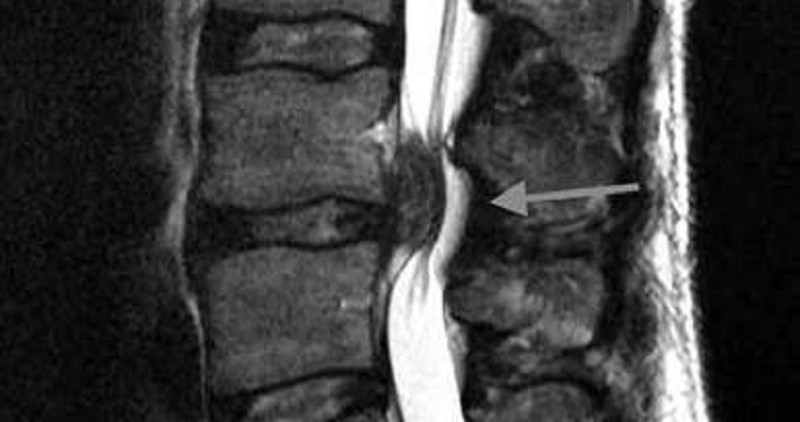

MRI

Röntgen LWS ap/seitlich im stehen